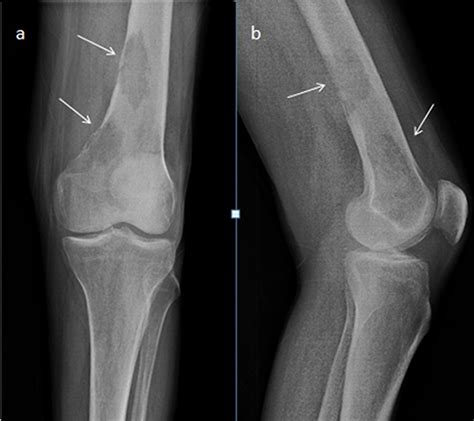

• Sunburst Pattern: Radiating spicules of bone formation that extend outward from the tumor into the soft tissue.

• Codman’s Triangle: A triangular formation of new bone that occurs when the tumor grows faster than the periosteum (the outer covering of the bone) can form new bone, resulting in an elevation of the periosteum.

Interpreting an Osteosarcoma X Ray requires a nuanced eye. Osteosarcoma is heterogeneous, meaning it can present in several different ways depending on its subtype and location. The appearance of the lesion often depends on whether it is predominantly osteoblastic (bone-forming) or osteolytic (bone-destroying).

When reviewing an Osteosarcoma X Ray, radiologists and clinicians do not work in isolation. The imaging findings are only as valuable as the clinical story behind them. A high index of suspicion is required when the patient—most commonly an adolescent experiencing a growth spurt—reports localized, persistent pain, swelling, or a reduced range of motion in a joint, particularly around the knee (the distal femur or proximal tibia).